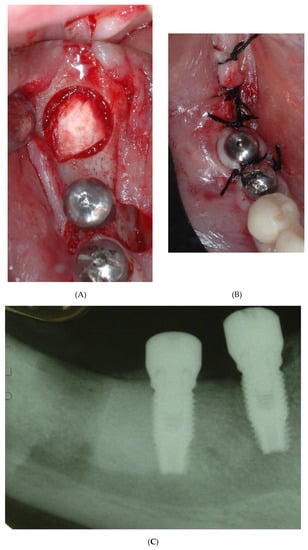

2. Case Report n.1

3. Case Report n. 2